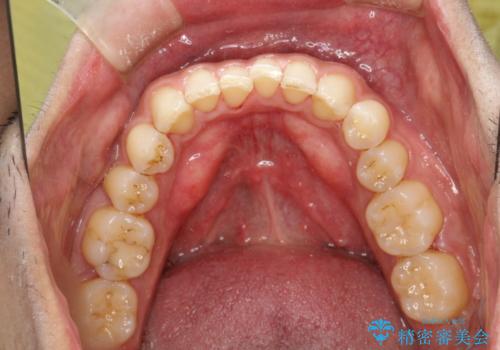

歯と歯の間の着色をPMTCでできる限り除去

- 歯と歯の間の着色を綺麗にしたいとのことで来院されました。PMTC60分で取れる範囲の着色や歯石などの除去を行いました。

毎日丁寧に歯磨きをしていても、日常生活での飲食物などにより着色してしまうことはあります。PMTCでは、歯の表面の凸凹にミネラルを補給して、ツルツルの表面に仕上げます